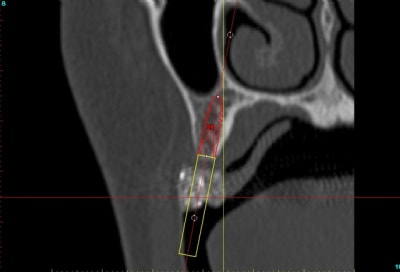

voilà, j'ai trouvé 5 mn...

le projet simplant est théorique, ça ne correspond pas à ce qui sera posé, c'était pour étude.

un autre exemple pour montrer que la visualisation est très correcte dans la technique en envellope: